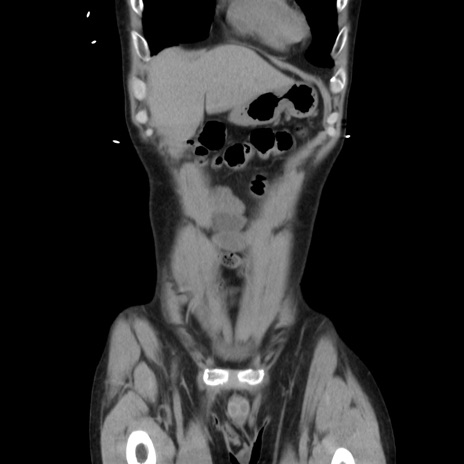

症例37(冠状断像)

【症例】40歳代 男性

【主訴】腹痛

【現病歴】4時間ほど前に電車に乗車中に臍部上より腹痛出現。徐々に増悪し起立困難となり、救急外来受診。生ものは数日食べていない。今朝お雑煮を食べた。

【身体所見】BT 36.8℃、BP 117/84mmHg、HR 91/min、SpO2 97%、苦悶様、腹部:臍上部広範囲圧痛あり、反跳痛±

【データ】WBC 8100、CRP 0.03